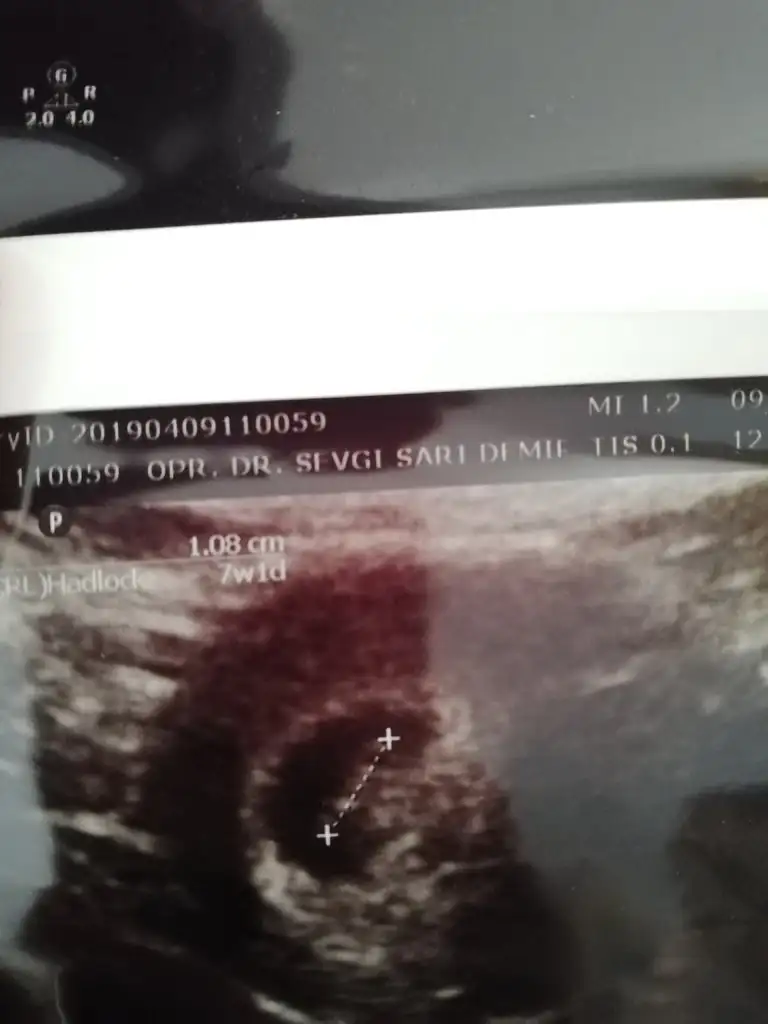

Kızlar şu nub teorisine göre bana da cinsiyetle ilgili bir yorum yapar mısınız 😀 7 haftalık usgyi ekliyorum.

Eklentiler

• IMG_20190426_093508.webp

IMG_20190426_093508.webp

17,7 KB · Görüntüleme: 50